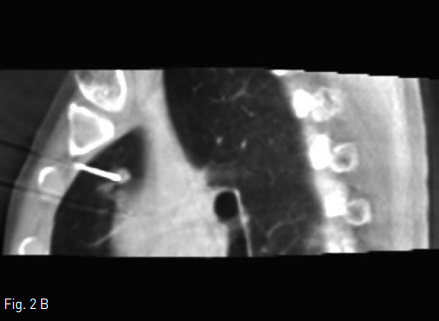

Fig 2A

Axial & sagittal cone beam CT (CBCT) scan show well targeted an electrode to the pulmonary nodule in RUL.

Fig 2B

Supine position에서 시행한 cone beam CT(CBCT)상 right lung의 upper lobe에 위치하는 약 7mm 지름의 결절은 관찰가능하였다. 통증조절을 위해 Lidocaine국소 마취와 Midazolam 2mg i.v. 하였다. CBCT guide 하에 2개의 2.5cm Octopus electrode(STARmed, Kyeonggi-do, Korea)를 병변에 삽입하였으며, 이중 upper electrode가 병변을 관통한 상태였고, lower electrode는 제거하였다(Fig.2). 12분간 RF ablation을 시행하였으며, CBCT상 병변 주변으로 ground glass opacty(GGO)가 형성된 것을 확인하였다 (Fig. 3). 마지막 CBCT상 RF ablation 으로 인한 volume loss로 인하여 mediastinal pleura 가 병변쪽으로 deviation된 것이 관찰되었고, 출혈, 기흉 등의 합병증은 없었다. 시술 중 통증은 경미하였다.